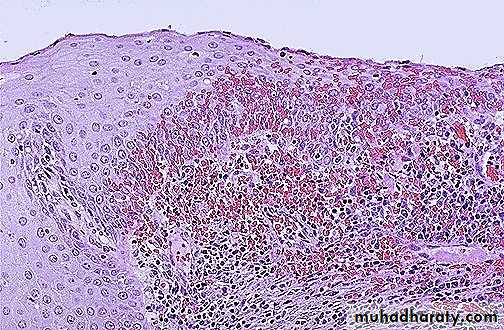

VIN: Dysplasia of the vulvar epithelium, seen here at the right with overlying hyperkeratosis , with more normal keratinizing squamous epithelium at the left.

A typical cytological changes (dysplasia) in the layers of the vulval squamous epithelium .Graded as VIN-1, 2, or 3 (mild, moderate, severe dysplasia /carcinoma in situ or Bowen disease).